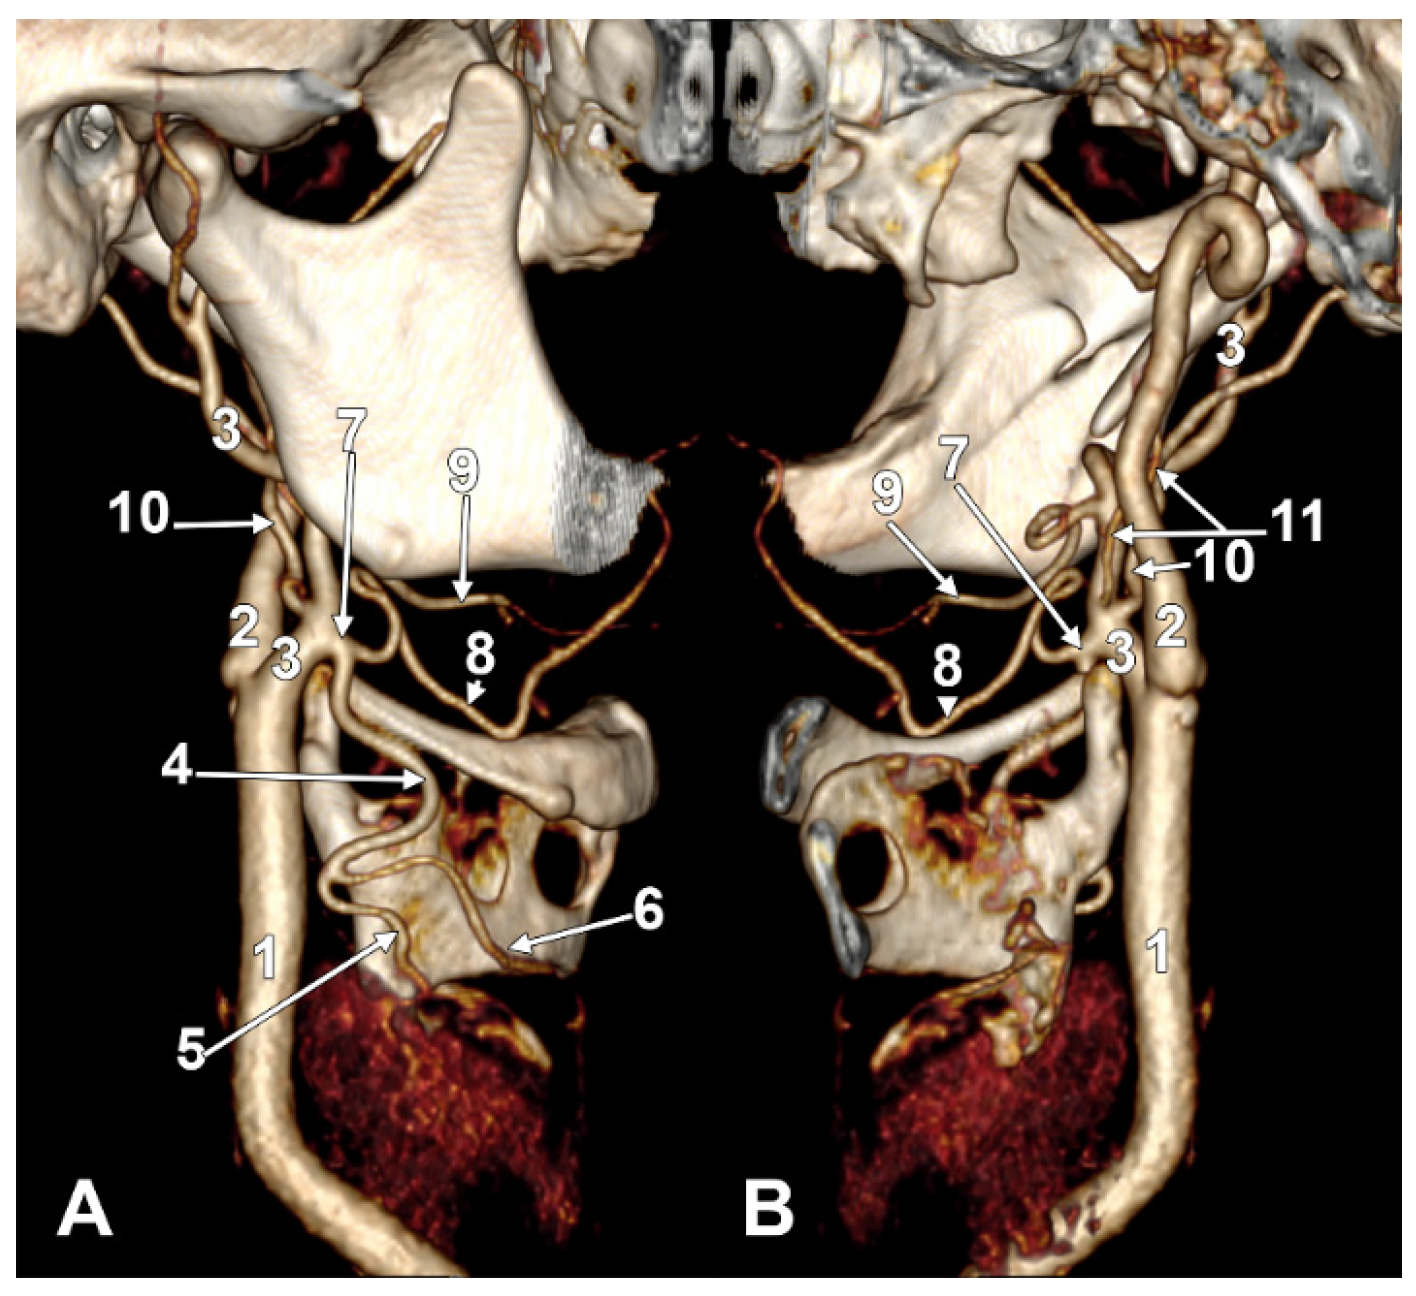

Figure 8. Long inferior petrosal sinus (arrowheads). Internal carotid origin of the ascending pharyngeal artery. Right side. (A) Anterolateral view. (B) Anteromedial view. 1. Common carotid artery; 2. internal jugular vein; 3. internal carotid artery; 4. external carotid artery; 5. superior thyroid artery; 6. lingual artery; 7. facial artery; 8. ascending pharyngeal artery; 9. styloid process; 10. body of the hyoid.

On the right side (Figure 7 and Figure 8), a 4.23 cm long styloid process was found, with a medial inclination of 72.4°. It crossed anteriorly, above the transverse process of the atlas, two veins: laterally—the internal jugular (IJV) vein, which had a transverse diameter of 5.94 mm, and medially—a long inferior petrosal sinus (IPS), with a transverse diameter of 3.15 mm. The IJV continued laterally to the transverse process of the atlas, and the inferior petrosal sinus, anterior to it. It was observed that the compression of the IJV occurs between the transverse process of the atlas and the posterior aspect of the digastric muscle. Also, the IPS appeared compressed at this level. The IJV had a minimum diameter of 1.21 mm, and the IPS had a minimum diameter of 1.08 mm. The IPS crossed laterally the ICA and APA, which, in turn, originated from the ICA (type IV), and continued medial to the ECA, crossed the origin of the FA, and descended anterior to the ECA, over the initial loop of the LA. The IPS and ECA coursed on the lateral side of the greater hyoid horn. Inferior to the hyoid, the IPS crossed the STA laterally and continued obliquely posteroinferiorly over the CCA, emptying into the IJV at 3.59 cm inferior to the CB. The APA on that side arose from the anteromedial wall of the origin of the ICA, at the hyoid level.

On the left side (Figure 9), the APA originated 8.9 mm posterosuperior to the tip of the greater hyoid horn from the posterior wall of the origin of the ECA, as its first branch. This was because the LA and STA arose via a common TLT from the CCA. The TLT origin was 8.8 mm inferior to the greater hyoid horn; the length of this common arterial trunk was 5.1 mm. It divided at 5 mm lateral to the superior horn of the thyroid cartilage into two vertical branches—an upper one, the LA, which ascended over the greater hyoid horn and made an upper loop before continuing with the hyoglossal segment, and a second, inferior one, the STA.